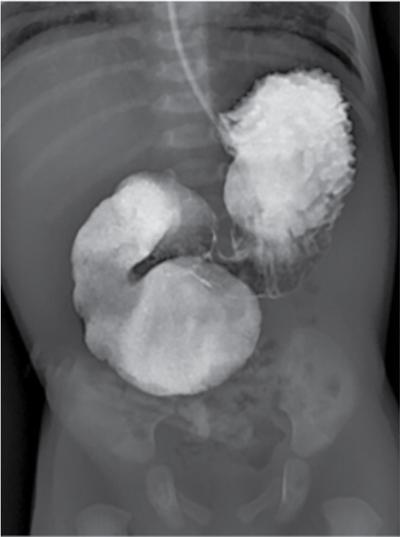

C.V. Kanimozhi, S. Muralinath, Raveendran J. Many of the important congenital gastrointestinal abnormalities present acutely in the newborn; some present much later. These include obstructive gastrointestinal lesions that present with vomiting, abdominal distension and not having passed meconium. The imaging modalities that are most commonly used in the evaluation of neonatal gastrointestinal abnormalities are plain films, contrast studies and ultrasound. Plain films remain a valuable tool in the assessment of abdominal abnormalities in the neonate. They are also an excellent guide to determining the next proper imaging study to perform for a particular problem. Certain neonatal bowel disorders have a pathognomonic appearance on radiographs obviating the need for further imaging. The essential and basic view to be done at the bedside is the supine view of the abdomen. In the evaluation of abnormal intra-abdominal gas patterns, alternative decubitus views, prone and supine cross-table lateral views may be taken. Erect view is not utilized in neonatal practice at the bedside as it is impossible to restrain a neonate in that position and unnecessarily subjects the neonate to stress, which may worsen the condition of an already sick baby. Evaluation of the bowel gas pattern and the anatomic localization of the intra-abdominal gas is the key to diagnosis in the evaluation of diseases of the GI tract. The bowel gas in the neonate is essentially swallowed air (Box 7.8.1). Movement of Air Through the GIT in a Term Neonate Most infants pass meconium by 24 hours of life. In order to interpret the bowel gas pattern and determine if an abnormality is present, it is crucial to know the age of the neonate (hours since birth) at the time the radiograph was taken. When there is impaired swallowing, such as due to CNS depression or in prematurity, radiographs show diminished bowel gas. In cases of bowel atresia, radiographs show absence of bowel gas in distal segments. Thus, the distribution of bowel gas and its pattern serve as pointers to the diagnosis. After the radiograph has been done, depending on the findings, an ultrasound or fluoroscopic contrast study may be performed next. The radiologist should tailor the contrast study to suit the particular patient and the clinical question that needs to be answered. In cases of suspected high GI obstruction, an upper GI contrast series is study of choice; in cases of suspected low GI obstruction a contrast enema should be performed to delineate the anatomy. When performing fluoroscopic studies, it is important to bear in mind the radiation dose and to adopt the ALARA principle. Minimizing radiation exposure in children is important because they are more sensitive to the effects of radiation and have a longer life expectancy than adults. The technical parameters must be adapted to paediatric imaging. Ultrasound is a useful bedside tool particularly in the sick neonate. In neonates, the sonographic image resolution is excellent due to the lack of significant body fat. In neonates, exquisite images of the abdomen can be obtained with the high-resolution ultrasound probe, which permits imaging the bowel wall in great detail. In addition, it can also reveal other causes for abdominal distension or vomiting. In this chapter, we will discuss the aetiology, clinical presentation and imaging appearances of congenital neonatal gastrointestinal abnormalities. We will also discuss common acquired abnormalities that present in the neonatal period, namely necrotizing enterocolitis. Congenital oesophageal malformations of the newborn include the various types of atresia (with and without fistula) and oesophageal duplications. Oesophageal atresia with or without tracheoesophageal fistula (TEF) is a common congenital anomaly that manifests in the neonatal period. It is also the most important congenital malformation of the oesophagus. Oesophageal atresia is commonly associated with other anomalies of the gastrointestinal tract such as imperforate anus, pyloric atresia, duodenal atresia and annular pancreas and less frequently with anomalies of the cardiac and genitourinary systems. About 20% of patients with oesophageal atresia have the VACTERL syndrome (vertebral anomaly, anorectal atresia, cardiac lesion, tracheoesophageal fistula, renal anomaly, limb defect). Oesophageal stenosis and webs may be associated with oesophageal atresia. The aetiology of oesophageal atresia and TEF is not completely understood. Faulty separation of the primitive trachea and oesophagus is the most widely accepted theory. The way the primitive foregut cleaves into a ventral (tracheal) passage and a dorsal (oesophageal) passage is a complex process and is poorly understood. Folds developing from the longitudinal ridge is said to separate the two. When the separation has an extreme tracheal bias, an oesophageal atresia occurs and if the bias is towards the oesophagus, then a tracheal atresia ensues. Incomplete separation may result in fistula of various types. Oesophageal atresia and TEF are classified depending upon the absence or presence and location of the fistula between the oesophagus and the trachea (Fig. 7.8.1). Neonates present within a few hours of birth with excessive salivation, drooling, cyanotic spells and regurgitation of feeds. The inability to successfully pass a nasogastric tube strongly suggests oesophageal atresia. Newborns with H-type fistula may have feeding difficulties and choking, but often the presentation and diagnosis is only later in infancy when the patient presents with cough, choking episodes and recurrent pneumonia. The role of imaging is to diagnose, define the anatomy to the best extent possible and evaluate for other anomalies to provide a clear picture for the paediatric surgeon. For example, it is important for the surgeon to know the side of the aortic arch in order to lateralize the surgical approach. Chest X-ray and Echo can localize the arch and determine if an anomalous right-sided aortic arch is present. Plain films of the chest including abdomen need to be obtained. The radiograph will demonstrate the air-filled distended proximal oesophageal pouch. If a nasogastric tube has been inserted, the coiled tube will be seen within the pouch. Absence of bowel gas in the abdomen indicates oesophageal atresia without a distal fistula – types A and B have this radiographic appearance (Fig. 7.8.2). The presence of gas in the gastrointestinal tract indicates the presence of a distal fistula – types C and D (Fig. 7.8.3). Contrast studies to delineate the proximal pouch are generally not indicated. Coiling of the nasogastric tube in the proximal pouch confirms the diagnosis. Chest radiographs frequently show changes of consolidation due to aspiration pneumonia, most often involving the right upper lobe (Fig. 7.8.4). In cases of H-type fistula, plain films are nonspecific and the diagnosis depends on contrast studies. Radiological diagnosis is made by means of a tube oesophagogram. This study has the potential risk of aspiration and the neonate may desaturate quite rapidly. Hence, it is important to have neonatal emergency resuscitation at hand. The tube oesophagogram is performed under fluoroscopy with the baby in lateral- or steep-prone oblique position. The NG tube is placed at the oesophagogastric junction and is gradually withdrawn while simultaneously injecting contrast. Nonionic low-osmolar contrast agent should be used. Most of the H-type fistulas are located in the lower cervical and upper thoracic regions with the fistula typically coursing upward and forward from the oesophagus. In the presence of a fistula, the contrast will be seen passing into the trachea in an upwardly oblique configuration. Aspiration during the study can also cause the contrast to appear in the tracheal tree and the lungs. It needs to be established whether the contrast has passed through the fistula or whether aspiration has occurred. Recording of the fluoroscopic run and reviewing the images may be required to make this distinction. Repeat examination may be required. Demonstration of H-type fistula can be difficult radiologically. In such patients, bronchoscopy with transfistula guidewire placement has been found to be of use. MRI – High resolution structural MRI is a new technique that is being used to visualize tracheobronchial anatomy. The disadvantage with radiographs is that one cannot determine the anatomic subtype of TEF, the site of the TEF or the length of the gap between the atretic segments. Using ultrashort echotime (UTE) MR imaging, it is possible to visualize the exact site of the fistula and assess the size of the oesophageal gap. This can aid presurgical planning and help identify infants at risk for complications, such as those with a long oesophageal gap. Imaging plays an important role in the evaluation of early and late complications of atresia repair. Early complications include anastomotic leaks and are seen in about 10%–20% of cases. Oesophageal contrast study, using a nonionic low-osmolar contrast agent, is performed to demonstrate the leak at the anastomotic site (Fig. 7.8.5). Leaks are associated with a greater incidence of subsequent stricture development. Anastomotic stricture is a common complication seen in about 30%–40% of cases. Often there is a slight narrowing at the site of repair without the patient having any difficulty in swallowing (Fig. 7.8.6). The anastomotic narrowing is clinically relevant only if the patient has dysphagia; such cases respond to dilatations. Recurrent TEF occurs in 5%–10% of cases after oesophageal atresia repair. Late complications include dysphagia, gastroesophageal reflux, tracheomalacia and chest wall deformities. Dysphagia can occur post-operatively due to abnormal oesophageal motility. Oesophageal dysmotility can be caused by abnormal neural development of the oesophagus or may result from complication of atresia repair. Gastroesophageal reflux affects 40%–65% of patients following oesophageal repair. It may be due to an intrinsic deficiency in the motor function of the oesophagus; this may get exacerbated postrepair due to an alteration of the anatomical gastroesophageal junction. Oesophageal atresia key imaging finding – X-ray shows NG tube coiled in proximal oesophageal pouch. The stomach is divided into the fundus and body proximally and the antrum distally. The antrum is divided by the sulcus intermedius into a proximal pyloric vestibule and a distal pyloric antrum or pyloric canal. This canal terminates into the pyloric sphincter beyond which is the duodenum. Congenital anomalies of the stomach that manifest in the neonatal period are uncommon. Hypertrophic pyloric stenosis (HPS) is the most common surgical cause of vomiting in infants. The incidence is 2–5 per 1000 live births, with geographic and racial variations. Compared to Caucasians, HPS is less common amongst Asian populations. The male to female ratio is approximately 4:1, occurring more commonly in the first-born child. The precise aetiology is unknown. Overactivity or prolonged spasm of the circular muscle of the pyloric antrum is thought to be the primary problem in these infants. This spasm leads to muscle hypertrophy and obstruction. Multiple hypotheses have been proposed for this prolonged spasm. One is that some infants are genetically predisposed to increased gastrin production which leads to a vicious cycle of hyperacidity, increased gastric contraction and secondary development of muscular hypertrophy. Most infants present after the first week of life and before 3–4 months of age. Typical symptoms include projectile nonbilious vomiting, regurgitation and difficulty in feeding. The gastric outlet obstruction can lead to emaciation. The distended stomach with active peristaltic activity may be visible through the thin abdominal wall. In the past barium upper GI series was the mainstay diagnostic tool for HPS. Prior to the barium study, the stomach may need to be decompressed via a nasogastric tube. The classic sign on a barium study is the ‘string sign’ (Fig. 7.8.7) produced by a thin stream of barium in an elongated narrowed pyloric canal; the canal typically curves upward. In severe cases, complete obstruction will lead to the ‘beak sign’, which is produced by beaking of the contrast as it enters the pyloric canal. With lesser degrees of obstruction, the ‘double track sign’ is seen. This is produced when the pyloric canal is flattened and the barium accumulates in the crevices along either side of the flattened canal. Pylorospasm can transiently mimic the findings of HPS. Currently, ultrasound is the modality of choice for the diagnosis of HPS and upper GI studies are seldom used. Ultrasound is considered the ‘gold standard’ as it allows direct examination of the pyloric muscle and also provides the ability to perform a dynamic study. The ultrasound examination is performed with a linear high-frequency transducer (6–10 MHz). The examination begins with the baby in supine position. First, the antropyloric region is identified; the pylorus is usually located medial and posterior to the gall bladder. The normal pyloric muscle is a thin hypoechoic layer that measures 2 mm or less. The abnormal pyloric canal shows thickening of the muscle and the mucosa to varying degrees. In cross section, it is seen as a hypoechoic structure likened to a doughnut. The length of the canal is measured in long section where its appearance is likened to the cervix. The sonographic diagnostic criteria for HPS are a thickened muscle layer measuring ≥3 mm and an elongated pyloric channel ≥15 mm (Fig. 7.8.8). The diameter of the pylorus in cross section was also one of the originally used measurements. However, due to a significant overlap between normal and abnormal, this measurement is no longer utilized. Additional ultrasound findings of HPS are hypertrophy of the pyloric mucosa and a distended, actively peristalsing stomach. The hypertrophied redundant mucosa projects into the antrum analogous to the ‘nipple sign’ in barium studies (Fig. 7.8.8D.). Colour Doppler imaging shows increased flow in the muscle and mucosa. The above-described measurements of pyloric muscle thickness and canal length are vital to diagnosis. However, dynamic assessment is equally important. One must evaluate the antropyloric region over a period of time to ensure persistent stenosis without evidence of relaxation and opening of the canal. A distensible antropyloric region with normal passage of gastric contents excludes HPS. Transient contractions of the pylorus or pylorospasm can mimic pyloric stenosis in both measurement and appearance. With observation over a period of time, opening of the pyloric canal may be visualized. Hence the key to diagnosis of HPS is persistent non-relaxing thickened musculature. Gas in the stomach may obscure the pylorus. To avoid this, place the infant in an oblique position, right side down which will allow the antrum to fill with fluid. Conversely, an overdistended fluid-filled stomach can displace the pylorus dorsally. In such cases, turning the infant left side down will displace the fluid towards the fundus and will allow the pylorus to rise to a more anterior position. At times, equivocal examinations may occur where the muscle measures 2–3 mm in thickness and does not relax. In these patients, careful monitoring with repeat ultrasound is warranted. In a few cases, the abnormalities advance overtime to fully developed HPS. Hence in such equivocal cases if vomiting continues, follow-up ultrasound is advisable. Surgical pyloromyotomy is the treatment for HPS. On ultrasound, the myotomy site can be seen as an interruption in the hypoechoic doughnut. It is important to be aware that postsurgery, the pyloric muscle may remain thickened for up to 5 months with a gradual return to normal thickness. In the first week after surgery, the muscle can be the same thickness as pre-op or even thicker. One should not be alarmed by this appearance. The dimensions gradually return to normal over the course of a few months. Postop if the child is thriving well, there is no need for imaging to be performed. HPS key imaging finding: On high-frequency ultrasound muscle thickness ≥3 mm and elongated pyloric channel ≥15 mm. Pyloric atresia is a rare anomaly comprising less than 1% of all intestinal atresias. Pyloric atresia is classified into three types (Fig. 7.8.9): The exact aetiology remains controversial. In the past, it was postulated that failure of recanalization of the gastrointestinal tract was the cause. Recent evidence suggests that pyloric atresia is the result of localized vascular occlusion. This vascular theory suggests that the atresia is due to focal ischemia secondary to intrauterine stress, vascular insult or anoxia. In complete obstruction, the presentation is in the neonatal period with nonbilious vomiting within the first few hours of life. Incomplete obstruction due to a diaphragm has a variable presentation depending on the size of the orifice. These patients can present later in life with intermittent vomiting or postprandial vomiting. In complete pyloric atresia, a dilated stomach is present on radiographs with absence of gas in the distal bowel. This is known as ‘single bubble’ appearance (Fig. 7.8.10). This appearance is diagnostic and in such cases, contrast studies are generally not required. In the membranous type, there is an opening in the centre of the diaphragm and hence, the obstruction is usually incomplete. On radiographs, the stomach is distended and lesser than normal volumes of air is present in the small bowel (Fig. 7.8.11). On upper GI barium studies, a diaphragm is seen as a thin (2–4 mm) linear filling defect that spans across the antrum with a normal pyloric canal. One needs to determine on fluoroscopy whether the membrane is causing significant obstruction or not. If obstructing, the diaphragm will balloon out with gastric peristalsis. In incompletely obstructing diaphragms, the edges of the diaphragm will be visible but there will no obstruction or ballooning. Pyloric atresia key imaging finding: X-ray abdomen – ‘single bubble’ appearance. Microgastria is an extremely rare congenital abnormality wherein the stomach is small, midline in position and typically associated with a dilated oesophagus. The stomach is represented by a small tubular structure without recognizable differentiation into fundus, body, antrum and pylorus. Agastria is the most extreme form of microgastria. Microgastria is frequently associated with other anomalies such as polysplenia-asplenia syndrome, malrotation, gastrointestinal atresia and vertebral, cardiac, renal and limb reduction anomalies (VACTREL association). Microgastria occurs due to arrest in early development of the foregut. In the 5th week of gestation, dilatation of the region of the future stomach occurs. Ninety-degree rotation of the stomach occurs in the 6th week, followed by development of the greater and lesser curves and growth of the fundus in the subsequent weeks. Arrest of this process leads to microgastria, with severity dependent on the stage at which arrest occurs. The development of spleen within the dorsal mesogastrium of stomach explains the association of microgastria and splenic anomalies. The association of limb, cardiac, tracheoesophageal, vertebral and renal anomalies has been attributed to impairment of early mesodermal development. The symptoms are related to the effects of the inadequate stomach and dilated oesophagus or due to the associated severe anomalies. These babies may present with feeding difficulties, failure to thrive, vomiting, recurrent aspiration and malnutrition due to severe gastroesophageal reflux. Radiographs may show an absent stomach bubble; in some cases, the shadow of the dilated oesophagus may be seen in the lower chest. On an upper GI study, the stomach appears small, tubular and midline in position. There is often associated severe gastroesophageal reflux and a very dilated oesophagus. The oesophagus dilates to take over the storage function of the inadequate stomach. Additional imaging studies are required to identify the associated anomalies. Key imaging finding: Upper GI study – Small, tubular stomach located in the midline. Congenital anomalies of the duodenum present with obstructive symptoms. The primary considerations for bilious vomiting in the neonate are duodenal atresia, duodenal stenosis, annular pancreas and malrotation with midgut volvulus. The most important investigation in the majority of these patients is an upper GI series as it accurately demonstrates the level and nature of duodenal obstruction. Duodenal atresia may be seen in isolation or in the setting of trisomy 21 (about 30% of patients have Down’s syndrome). Associated anomalies are frequent and include malrotation, oesophageal atresia, annular pancreas, biliary atresia, congenital heart disease and vertebral anomalies. Duodenal atresia is due to failure of gut recanalization during embryologic development leading to complete obstruction. Normal recanalization of the duodenum occurs between the 9th and 12th weeks of gestation. Failure of this process results in duodenal atresia. In most cases (roughly 80%), the atresia is distal to the ampulla of Vater. Neonates with duodenal atresia present with bilious vomiting in the first few hours of life. In those patients where the atresia is proximal to the ampulla, the vomitus will be nonbilious. In duodenal atresia, air is present in the stomach and duodenum with no gas in the distal intestinal tract. Dilatation of the stomach and the duodenum produces the characteristic ‘double bubble’ appearance on radiographs (Fig. 7.8.12). This appearance is diagnostic and rarely requires further imaging. Key imaging finding: X-ray abdomen – ‘double bubble’ appearance Duodenal stenosis and duodenal web cause partial obstruction due to a narrowed segment or thin membrane, respectively. As with duodenal atresia, both these conditions show a strong association with malrotation, annular pancreas and a preduodenal portal vein. Duodenal web and stenosis is due to incomplete recanalization of typically the second part of the duodenum. In babies with duodenal stenosis, the presentation and clinical findings depend on the degree of stenosis. Those with less severe forms of stenosis may present later in life. Radiographs in duodenal stenosis and web show a distended stomach and duodenum. Since the obstruction is incomplete, gas will be present in the distal loops. On upper GI study, duodenal stenosis is seen as a focal narrowing in the second part of the duodenum (Fig. 7.8.13). In duodenal web, a thin membrane/diaphragm is seen that partially obstructs the lumen, usually in the second segment of duodenum. The membrane is often difficult to demonstrate (Fig. 7.8.14). A ‘windsock deformity’ may also be seen; this appears as a proximal dilated duodenal segment with contrast outlining a thin web that bulges into a distal nondilated segment. This windsock duodenum is seldom seen in the neonatal period as this appearance is due to stretching of the membrane over time. Key imaging finding: Upper GI study – narrowing in second part of duodenum. Annular pancreas is an anomalous band of pancreatic tissue that encircles the second portion of duodenum. Annular pancreas may result in extrinsic duodenal obstruction. Often there is associated intrinsic duodenal abnormality viz. some degree of duodenal atresia, web or stenosis. As in duodenal atresia, associated anomalies such as trisomy 21, cardiac defects, malrotation, oesophageal atresia and anal atresia can occur. The pancreas arises as two endodermal outgrowths, ventral and dorsal buds, from the duodenum. The head of the pancreas derives from the smaller ventral bud. Annular pancreas occurs if the ventral bud becomes tethered to the duodenum or it fails to rotate completely before fusion with the dorsal bud. The clinical presentation is similar to duodenal atresia or stenosis. If the obstruction is complete, presentation is in the neonatal period with bilious vomiting. Cases of incomplete obstruction may remain asymptomatic until adulthood. Annular pancreas is the second most common condition to produce a ‘double bubble’ appearance on radiographs. Plain films will show dilatation of the stomach and duodenum. Upper GI contrast study will show narrowing of the second part of duodenum (Fig. 7.8.15). On ultrasound pancreatic tissue may be seen encircling the second part of duodenum (Fig. 7.8.16). At times the appearance may resemble a mass at the level of head of pancreas.